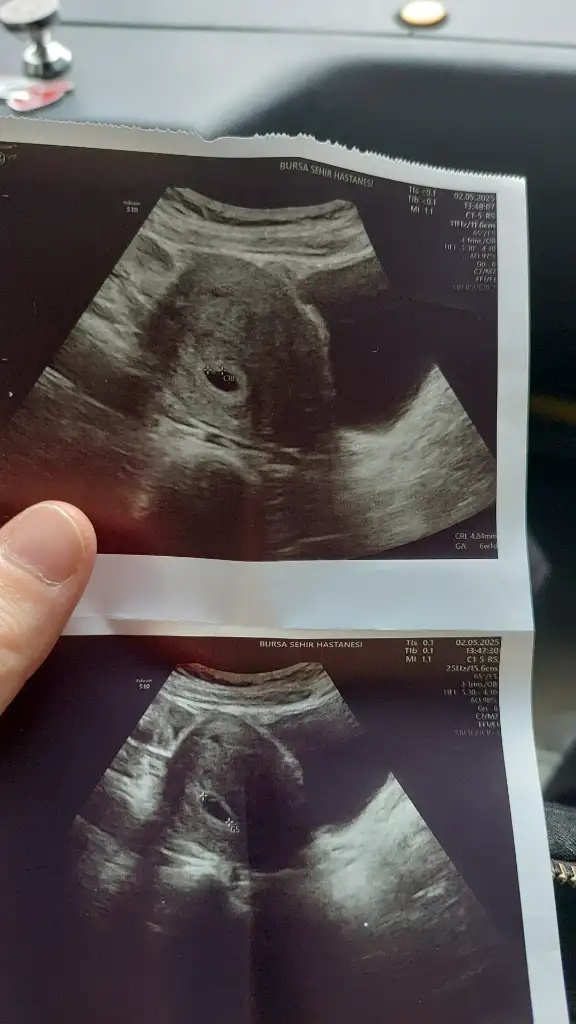

Banada bakar misini 6+1 karından ultrasonKızlar 6-8 haftalık ultrason görüntülerinizi atın tahmin yapalım . Ya da cinsiyeti öğrenen annelerimiz 6-8 haftalık görüntülerini atsın bize de fikir olsun

Kıza benziyorKızlarr benimkinin cinsiyetini de tahmin edebilir misiniz biraz küçük ama merak iştekarından ultrason sat 6-6 doktora göre 6-3